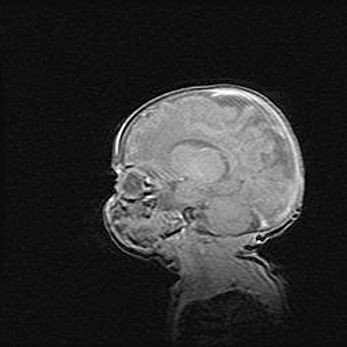

Открытая гидроцефалия.

Возраст: 9 месяцев 12 дней

Вес: 6800 г

Пол: мужской

Окружность головы: 41,5 см

Срок гестации: 28 недель

Гидроцефалия головного мозга у новорожденных имеет характерный признак: опережающий рост окружности головы приводит к визуально хорошо определяемой гидроцефальной форме сильно увеличенного в объёме черепа. Детские неврологи определяют следующие симптомы гидроцефалии у грудничков: выбухающий напряжённый родничок, частое запрокидывание головы, смещение глазных яблок к низу.